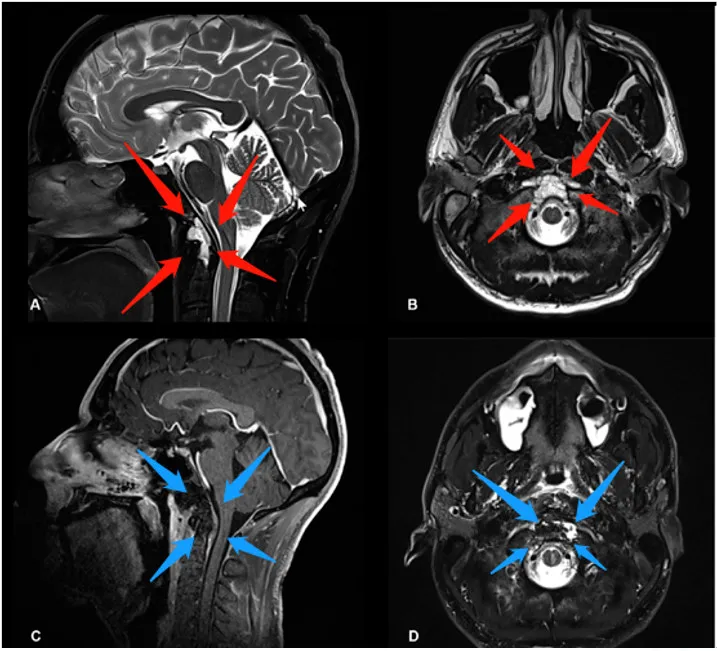

福洛里希教授案例解析 国际神经外科联合会(WFNS) 颅底手术委员会前主席, 发表了筷子技术神经内镜联合显微镜双镜联合 全切颅颈交界区较大脊索瘤手术研究成果。 其中一例国际疑...